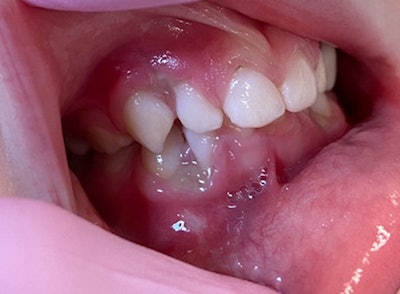

9.5-year-old girl with gingival lesions

A 9.5-year-old girl presented to the oral surgeon’s office, referred by her family dentist, because of painless "growths" on her anterior maxilla. The patient told the surgeon that the lesions had been present for the last 10 months but had increased in size within the last month. The patient was asymptomatic.